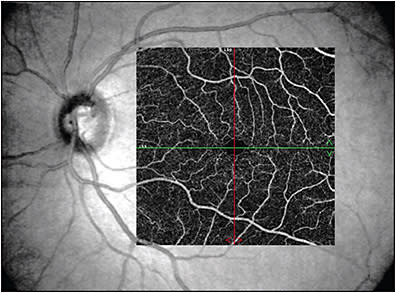

Imaging modalities have long been integral to ophthalmology in clinical and research settings. In 1991, the introduction of optical coherence tomography (OCT) became a pivotal milestone in noninvasive imaging of the retina and optic nerve in vivo.1 Its utility has been critical in both studying and managing pathology throughout nearly all layers of the anterior2-6 and posterior7-10 segments. In 2006, another milestone was achieved in ocular imaging as Makita et al described optical coherence tomography angiography (OCTA), which built off of the OCT platform and thus provided a new modality to perform noninvasive angiography of the eye with macular images comparable to dye-based angiography (Figures 1 and 2).11 Optical coherence tomography angiography is a functional extension of OCT technology to visualize the retinal and choroidal vasculature. The end result is a full-thickness retinal angiogram with images segmented into the superficial retinal plexus, deep retinal plexus, outer retina, and choriocapillaris.12 It is not only fast (acquiring 3-dimensional scans in a matter of seconds),13 but also, in being noninvasive, it avoids the rare but potentially serious adverse reactions ranging from nausea to anaphylaxis associated with dyes used in angiography, such as fluorescein or indocyanine green.14-16